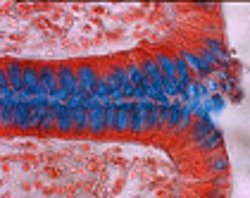

Immunregulation der Epithelzellbarriere im Darm

Mitochondriale Regulation im Darmepithel

Epithelialer Metabolismus bei Infektion und Entzündung im Darm